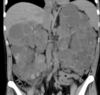

What do you see here?

Acute interstitial nephritis